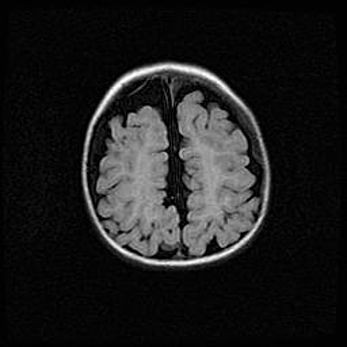

Открытая гидроцефалия.

Возраст: 9 месяцев 12 дней

Вес: 6800 г

Пол: мужской

Окружность головы: 41,5 см

Срок гестации: 28 недель

Гидроцефалия головного мозга у новорожденных имеет характерный признак: опережающий рост окружности головы приводит к визуально хорошо определяемой гидроцефальной форме сильно увеличенного в объёме черепа. Детские неврологи определяют следующие симптомы гидроцефалии у грудничков: выбухающий напряжённый родничок, частое запрокидывание головы, смещение глазных яблок к низу.